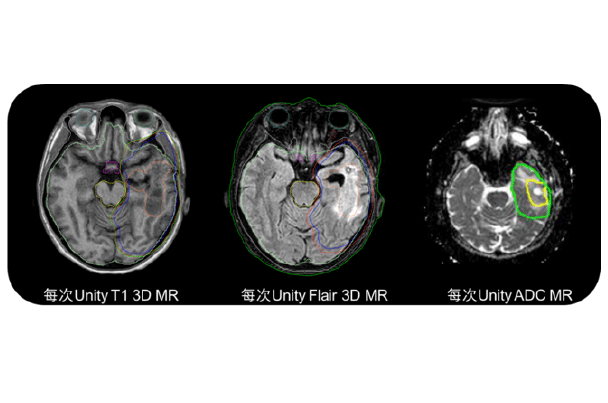

磁共振脑组织成像比传统X线或CT成像模式相比,肿瘤自身和周围健康脑组织成像分辨更高,多模态成像结合让靶区勾画更加精准,投照更加精确,对健康脑组织保护更加。治疗过程中可针对肿瘤变化,采用不同的扫描序列成像知道自适应治疗方案调整。未来的磁共振功能成像技术也为后续治疗方案的设定提供指导依据。